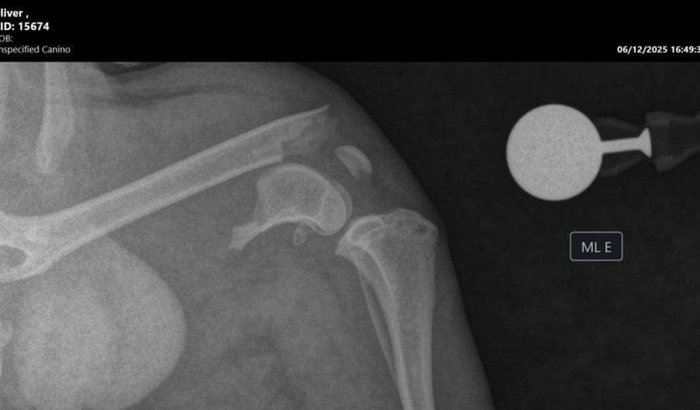

Vaquinha criada em: 11/12/2025

Oi, meu nome é Oliver! Fui abandonado dia 05/12 e em seguida atropelado. Fui parar na calçada de uma moça que ama animais e me viu sangrando e com a patinha machucada. Ela cria 9 gatos e não tem condições de pagar meu tratamento. Mas mesmo assim ela me levou pra casa, me deu remédio, me levou pra fazer raio x, e meu fêmur está completamente quebrado. Ela começou uma vakinha pra pagar minha cirurgia, medicações e fisioterapia. Tentou em clínicas gratuitas, mas não conseguiu. Meu caso é muito sério e de emergência, e preciso de você. Por favor DOE QUALQUER VALOR.

A cirurgia é R$ 1.400 e a fisioterapia R$ 1.400.